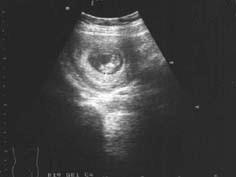

问题 患者女24岁,停经65天,B超检查如图所示,应诊断为 ( )

选项 A、绒Ca B、子宫肌瘤 C、宫内积血 D、葡萄胎 E、早孕

答案 E